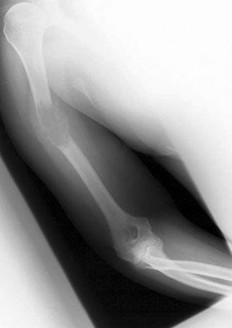

A 15-year-old male presents with deep knee pain awakening him at night. Radiographs show a permeative destructive lesion in the distal femoral metaphysis with a 'sunburst' periosteal reaction and Codman's triangle.

Biopsy confirms high-grade conventional osteosarcoma. What is the most critical prognostic factor for long-term overall survival in this patient?

Explanation

For localized high-grade osteosarcoma, the most important prognostic indicator is the histologic response to neoadjuvant chemotherapy. This is evaluated during the definitive resection. A 'good response' is typically defined as greater than 90% or 99% tumor necrosis. Patients who achieve this level of necrosis have a significantly improved disease-free and overall survival rate compared to 'poor responders' who have extensive viable tumor cells remaining.